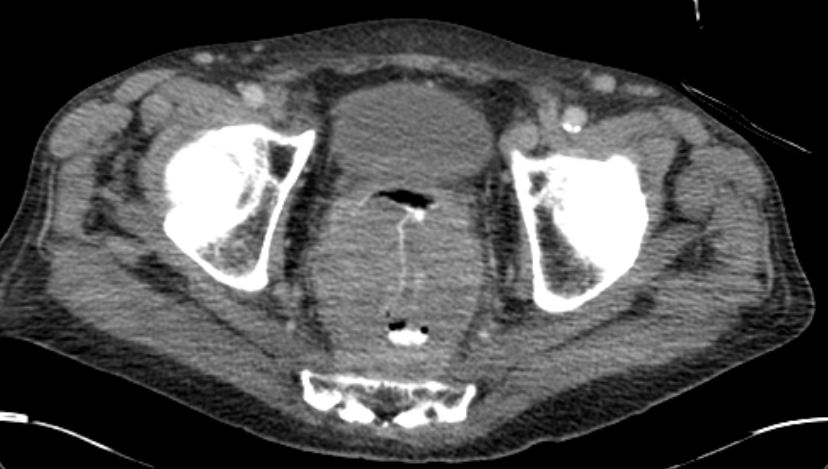

| Colitis | 77-jähriger Mann, der vor 2 Jahren mit Colitis ulcerosa eingeliefert wurde. Das CT zeigte eine diffuse Wandverdickung des gesamten Kolonrahmens mit Infiltration des umgebenden Fettgewebes. Umschriebene Perforation des Rektums nach ventral zur Prostata ohne Nachweis einer rektrourethralen Fistel. Endoskopie mit Biopsien: keine Malignität. | |

| Tumor | Jetzt Wiederaufnahme wegen eines akuten Schubs der Colitis ulceosa. Ausgedehnter Rektum - Tumor, welchen das kleine Becken ausfüllt. Zirkuläres, exophytisch und ulzerierend und infiltrierend wachsendes Karzinom im Rektum und Analkanal. Lebermetastasen. | |